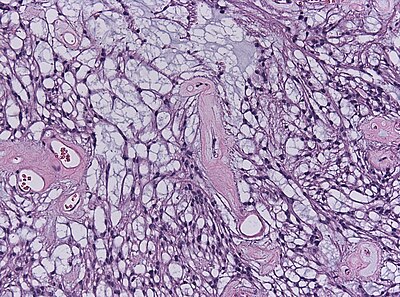

3

Diagnosis?

Neuropathology case V 03.jpg

Pilocytic astrocytoma

Diffuse Astrocytoma

Pleomorphic xanthoastrocytoma

Subependymal giant cell astrocytoma

Oligodendroglioma

Glioblastoma, classic

Glioblastoma, epitheloid

Giant cell glioblastoma

Gliosarcoma

Ependymoma

Subependymoma

Myxopapillary ependymoma

Ganglioglioma

Choroid plexus papilloma

Angiocentric glioma

Dysembryoplastic neuroepithelial tumour

Neurocytoma

Paraganglioma

Pineocytoma

Papillary glioneuronal tumour

Medulloblastoma

CNS PNET